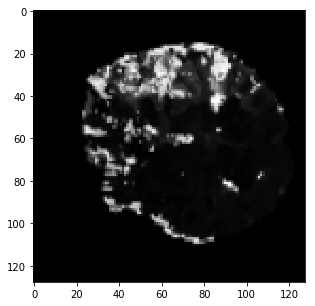

The qualitative results are shown in Fig. 2. Addition of LS and BD losses while training the network significantly improves the boundary delineation in the results. This improvement is more drastic when the network is adversarially trained as seen in the results of the proposed method as compared to BL7.

[TMax]

\subfigure[TTP]

\subfigure[DWI]

\subfigure[GT]

[BL3]

\subfigure[BL4]

\subfigure[BL7]

\subfigure[Proposed]